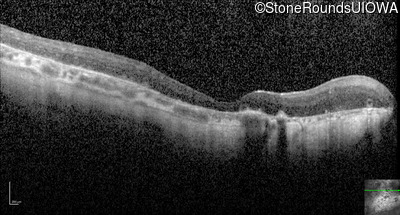

Optical Coherence Tomography - Left - Light Perception

Exemplar / OCT Stack